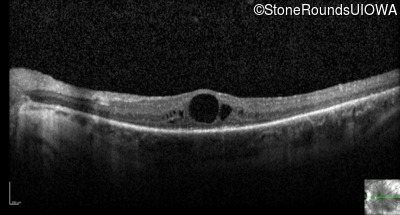

Optical Coherence Tomography - Left - 20/70 +1

Exemplar / OCT Stack